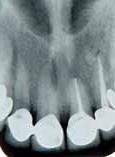

posteriorly on the left palate till the posterior vibrating line. There was no pointing of the lesion. IOPA and occlussal radiographs were taken (Fig1a & b). The IOPA revealed a huge radiolucent lesion with diffuse margins in relation to the periapical region of the upper left lateral which had a root canal filling and a separate smaller radioluscent periapically to the adjacent central incisor also. The occlussal radiograph showeda large radiolucent lesion on the palatal aspect in relation to the upper left lateral. It was decided to retreat the case and the patient was advised of the poor prognosis of the tooth.

Fig 1a: First visit (IOPA) Fig 1b: first visit (occlussal) Fig 2a: Pre obturation 14 months (IOPA) Fig 2b: Pre obturation 14 months (occlussal)